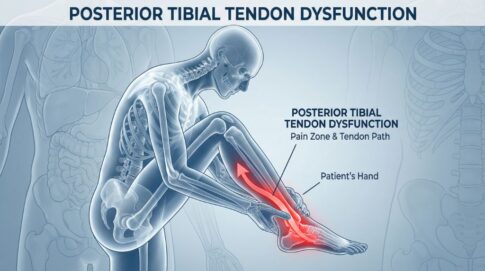

足首の外側靭帯損傷(捻挫)が最も多い理由

整形外科で最も多い外傷とされ、日本全国で1日あたり約1万2000人が足首の捻挫を経験しています。

- スポーツ中の急な方向転換時の捻挫

- 日常生活での段差での足の踏み外し

- 階段の上り下りでの不注意な動作

- 過去の捻挫の不十分な治療による後遺症

足首の痛みが慢性化する原因

足首の痛みが慢性化する主な原因は、初期治療の不十分さと全身のバランス異常

海外の研究によると、足首捻挫患者の約20-40%が慢性的な症状を訴えることが報告されています。

- 足首周囲の筋力不足による再発

- 関節の可動域制限

- 神経系の協調性低下

- 全身の姿勢バランスの崩れ